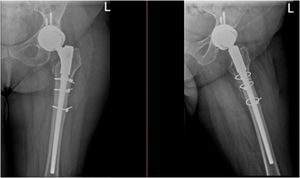

Materiales y métodosRealizamos un estudio retrospectivo de pacientes sometidos a artroplastia de revisión para el tratamiento de fracturas del vástago femoral periprotésico. Revisamos a todos los pacientes ingresados en nuestra Institución entre 2010 y 2020, con fracturas periprotésicas de tipo B2 y B3 de Vancouver, e incluimos a todos los pacientes tratados mediante artroplastia de revisión con vástago cónico estriado modular no cementado (fig. 2). Se excluyó a los pacientes con menos de un año de seguimiento, o sometidos a osteosíntesis. También se excluyó a los pacientes tratados con revisión acetabular simultánea. El estudio fue aprobado por el Comité de ética de nuestro centro. Al tratarse de un estudio retrospectivo se obtuvo la exención del consentimiento informado.

El vástago utilizado en la revisión fue MRP-Titan (Peter Brehm, Weisendorf, Alemania), que se trata de un vástago cónico modular no cementado formado por un vástago fijado distalmente con longitudes variables, una sección metafisaria para ajuste de la longitud de la pierna, y una porción de cuello con opciones normales y lateralizadas que permite un ajuste de versión de 360° para mayor versatilidad. El vástago de titanio cuenta con bordes longitudinales que promueven el crecimiento óseo interno, la preservación de stock óseo y la estabilidad rotacional inmediata. El acoplamiento vástago-cuello se realiza utilizando una unión de cono morse junto con un perno específico del torque.

En casos que presentaran fractura del trocánter mayor (GT), se añadió osteosíntesis con placa o cables, de acuerdo con la decisión del cirujano.